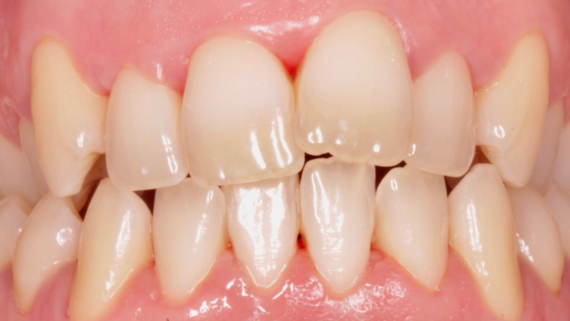

Este paciente acudió a Clínica Dental Urumea para mejorar la estética de su sonrisa. Primero se realizó un tratamiento de ortodoncia con alineadores transparentes Invisalign, para alinear y corregir la mordida cruzada.